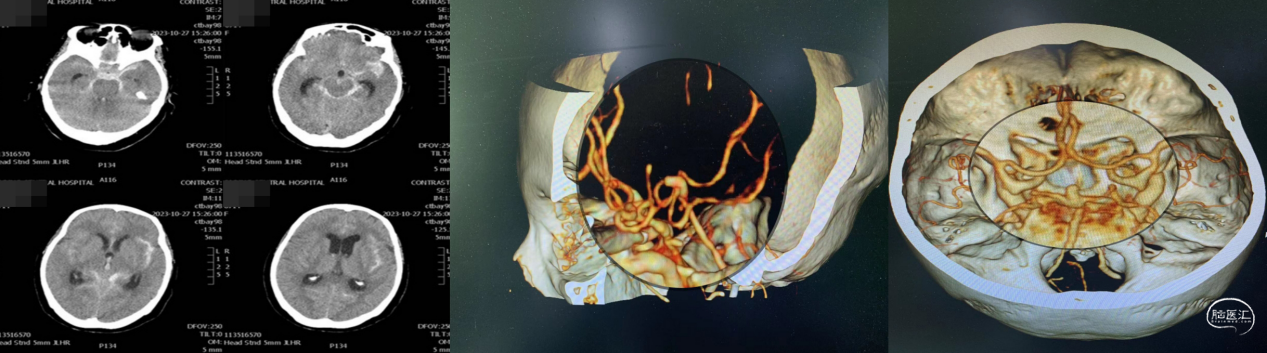

近期,中国医科大学附属第一医院卒中中心李志清主任(点击进入个人主页)及其团队采用球囊接力技术成功救治颈动脉全程闭塞致急性脑梗死患者。现患者恢复良好,已顺利出院。

点击查看原文:《医路前行|卒中中心采用球囊接力技术成功救治颈动脉全程闭塞致急性脑梗死患者》